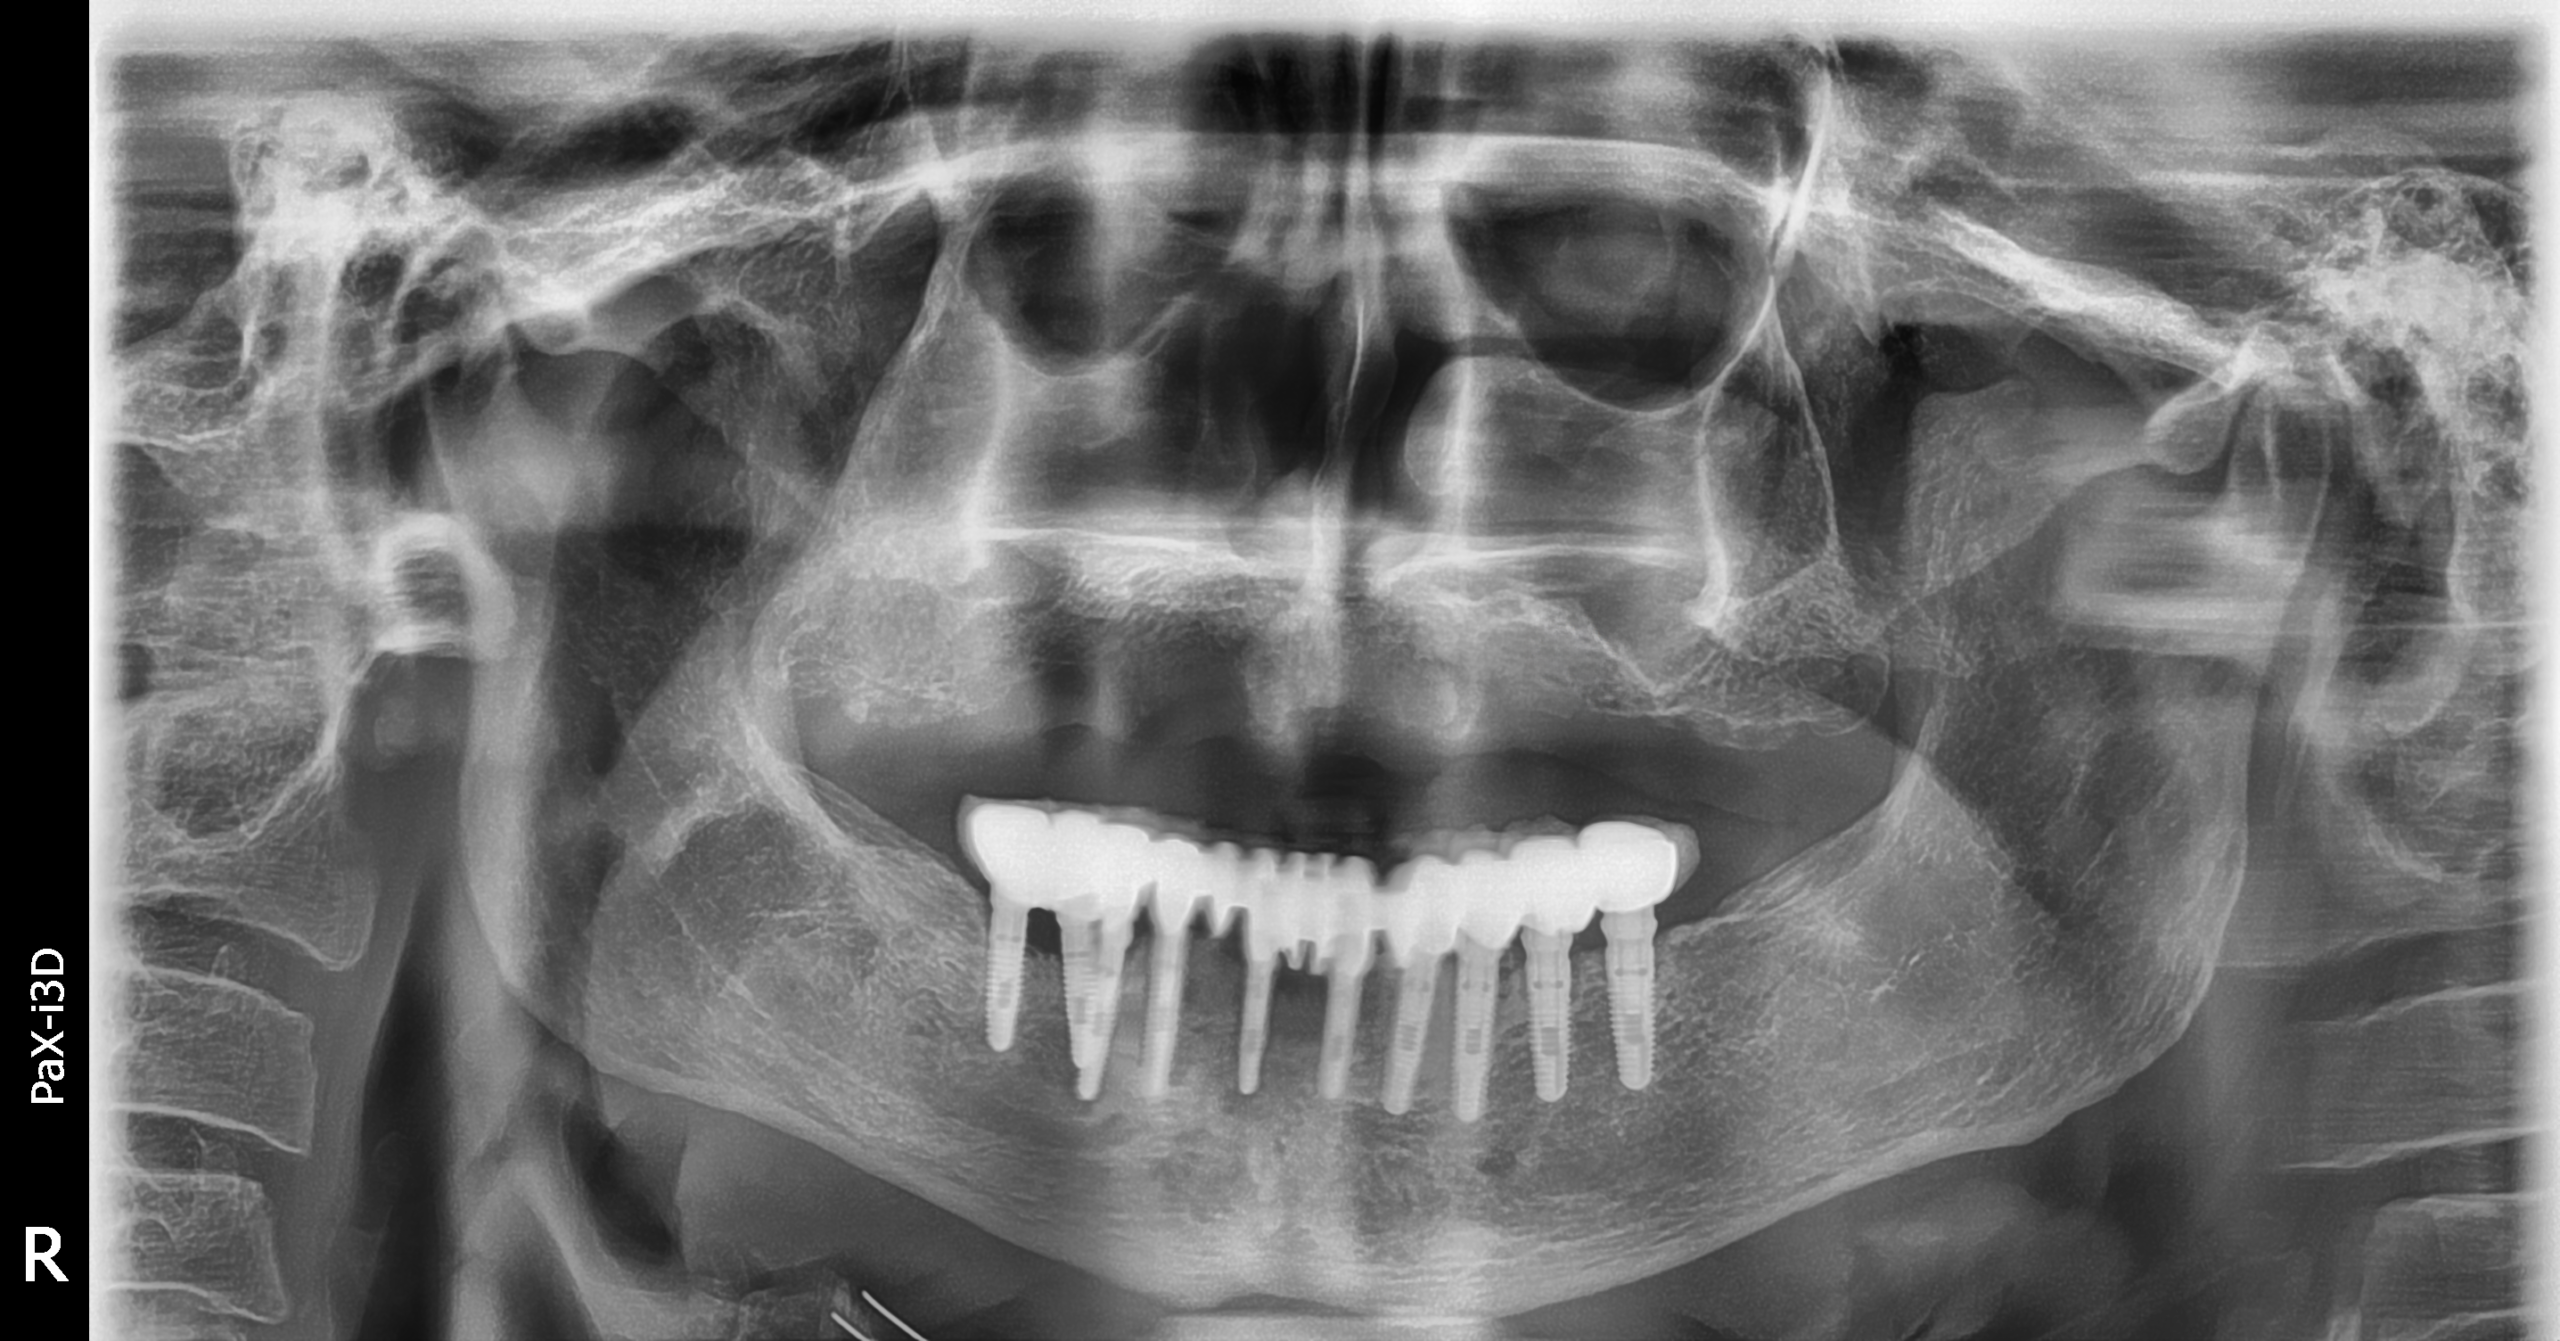

Implantes PCI

Secuencia de imágenes RX, antes y después de la inserción de implantes PCI en la parte superior e inferior de la boca.

Paciente varón de 75 años.

- Radiografía previa a la colocación de implantes Radhex.

- Colocación de implantes Radhex PCI en la parte superior

- Colocación de implantes Radhex PCI en la parte inferior.